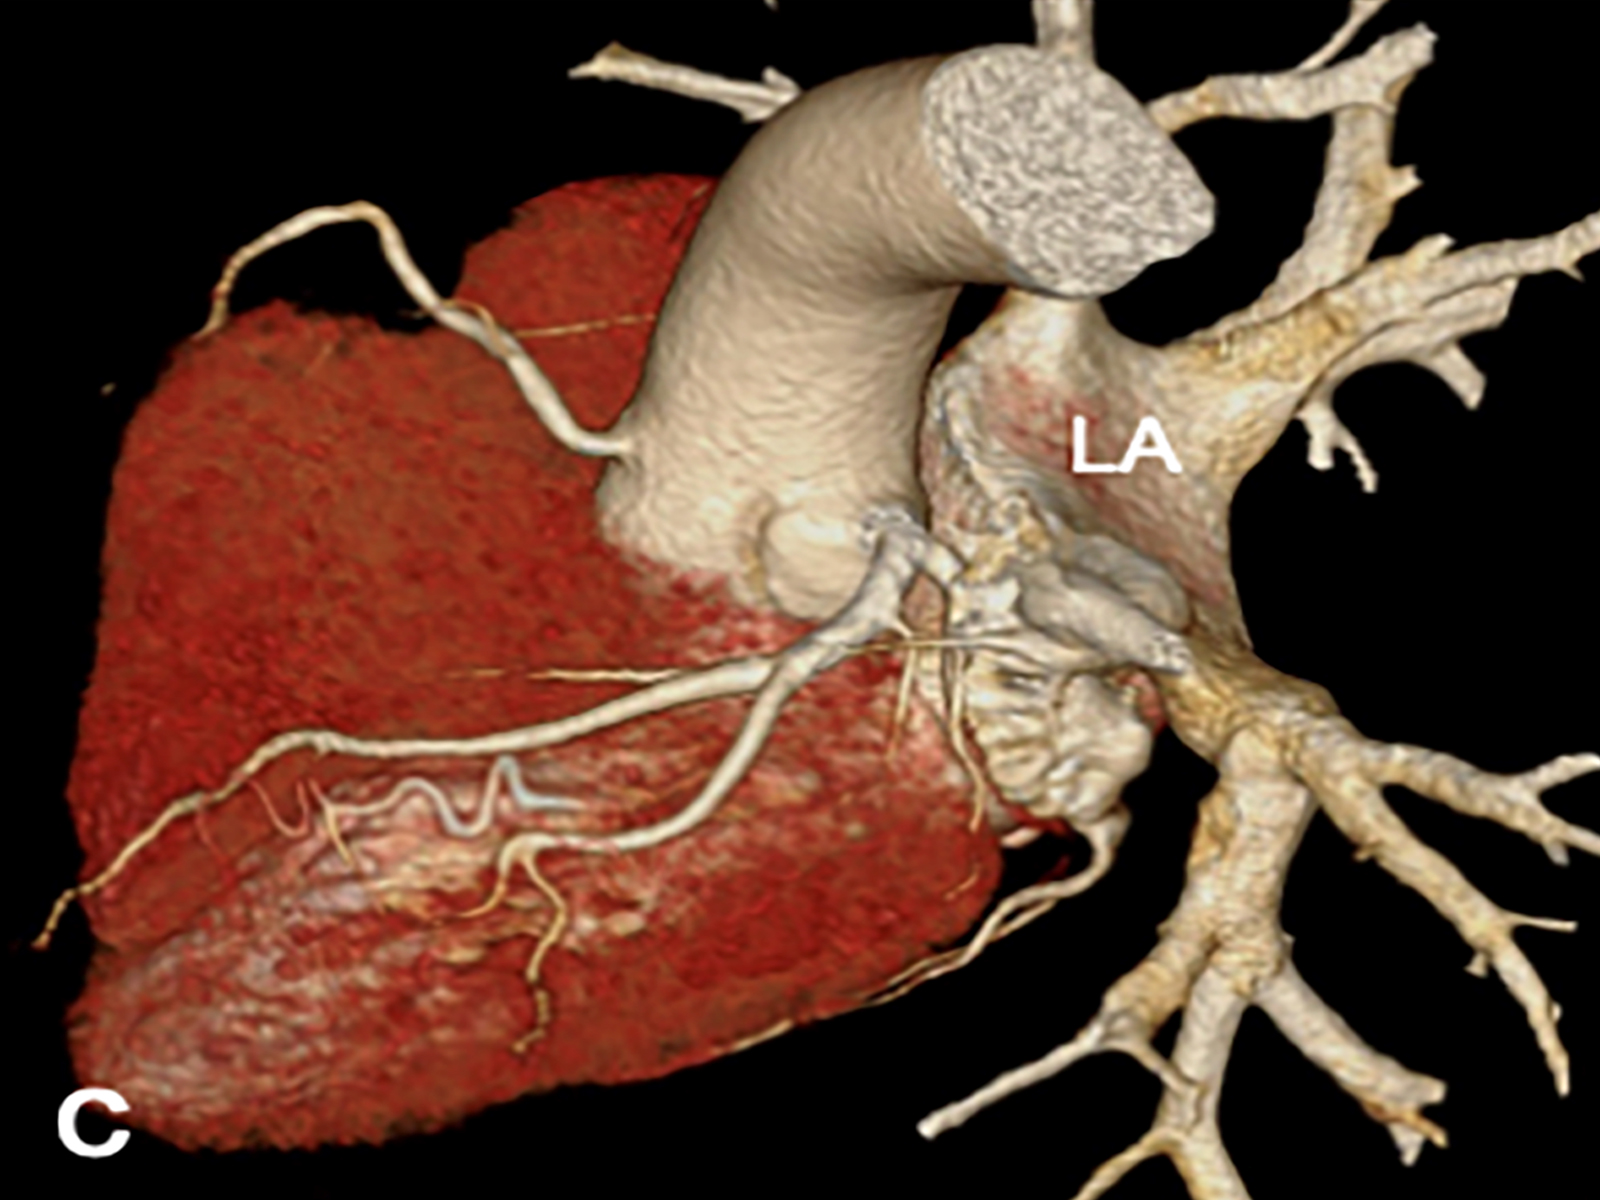

Massive Hemoptysis in Bronchial Dieulafoy’s Disease: Suspect Early

Shengquan Wei, Huixia Wang, Tiantian Lv, Gen Li, Ruzhen Jia doi: 10.5505/respircase.2026.24855 Pages 5 - 7 |